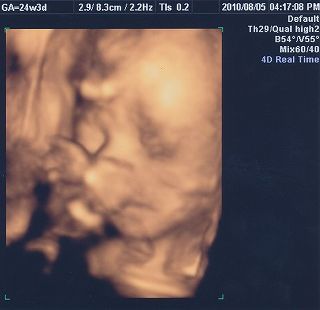

11月11日(木)に出産して、13日(土)から母子同室開始。 今までは、Håkichiの授乳以外は寝るかテレビを見るかだけだったんだけど、同じ部屋にHåkichiがやってきて、Håkichiの観察が勢いを増します(笑) この時に一緒にでる声がまた可愛い♪ なぜか手が異様に白いんですけど・・・・・マミーとダディがほどよくミックスされてるならいいんだけど、パーツごとに違うのは怖いのでやめてください(汗) そして予定日より2週間ほど早くこの世界に出てきたHåkichi。本人はまだ私のお腹の中にいると思っているのか、自然に壁の方に移動していって側面にタッチ。 Håkichi、何度ベッドの中央に戻しても、側面目指して移動し、手と足だけにとどまらず、顔までくっつけてました。 HåkichiはJ君によって非常にコンパクトにまとめられました。 さてここから、新米マミー&ダディにより子育てが始まるわけなんですが、退院した当日は家に帰って何をしていいか分からず、とりあえず2人で観察。 そして翌日。おむつ交換、授乳以外のほかに新たな試練が!! そう、沐浴です。沐浴指導は退院前日に1回やったのみで、まるで自信なし。しかも私たちが実践しようとしている沐浴は普通の沐浴とは違うし・・・ ベビーバスを購入するに当たって、一般的なものは1ヶ月くらいで使わなくなってしまうというのを聞いていたので、私たちが選んだのは ↓ ↓ ↓ ↓ Tummy Tub (←公式ウェブサイト) 「ママのお腹にいた時と同じ、赤ちゃんがいちばん落ち着ける姿勢で沐浴できる」というコンセプトが気に入り、プラス私とJ君が普段からシャワー浴しかしないので、Håkichiをお風呂気分にさせてあげるのはこれが一番かなと思い購入。2歳頃まで使えるらしいし、数年後Håkichiが巨大化しこのタブが使えなくなったら、他の使い道がありそうだし。 という事で、Håkichiをタミータブに入れてみたんだけど、Håkichiがあまりにも小さくてタブの中に埋もれてしまいそうになりパニクる+ブチ切れるJ君。仕方がないので、私がキューバにいた時に足浴に使っていたたらいを使用。 何も知らないHåkichiは幸せそうにお湯に浸かってます。 お湯に浸かっているときはいいんだけど、その後が大変! Håkichiをタオルに包みキッチンのシンクからリビングへ移動し、服を着せるんだけど毎回のように大泣きするHåkichi。数日がこの繰り返しで、移動の最中に泣き始めていることを発見してからは、キッチンにハイローベッド(これもまた優れもの!!)を置き、そこでササっと着替えることに。すると大泣きすることもなくなりました。ほっ。こうやって試行錯誤しながら親になっていくんですね~。 そして新米マミー&ダディのドタバタ劇に付き合わされ、疲れ果てた(?)Håkichiは再び天使のような顔で眠りにつくのでした。 Håkichi、君は本当によく寝る子で母さん嬉しいよ☆ ※ちなみに新生児時代にお蔵入りになったTummy Tubですが、もうすぐ4ヶ月になるHåkichiには大活躍!! その様子はまた後日お知らせします。 |